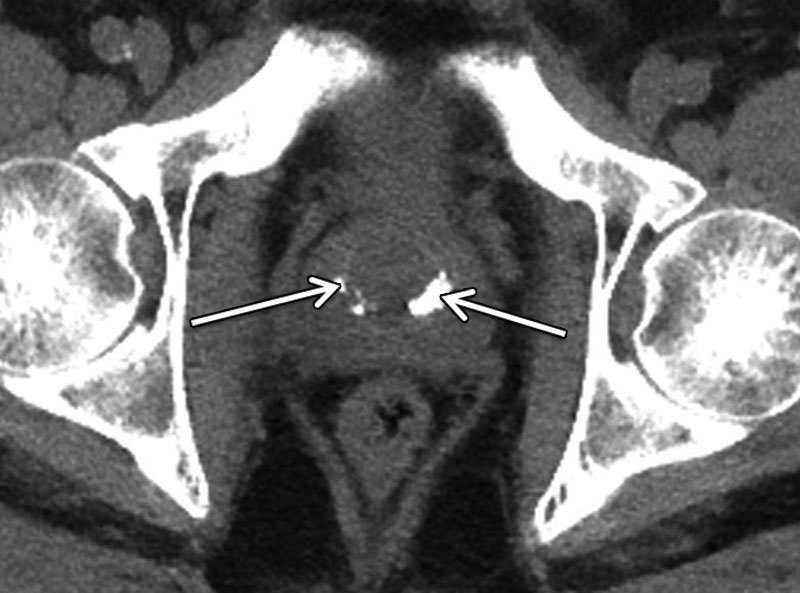

Vôi hóa tuyến tiền liệt xảy ra khi canxi tích tụ trong tuyến tiền liệt. Mặc dù nguyên nhân chính xác vẫn chưa được xác định nhưng thường có liên quan đến các tình trạng tiềm ẩn như viêm tuyến tiền liệt, phì đại tuyến tiền liệt hoặc phẫu thuật ung thư tuyến tiền liệt trước đó. Kích thước của những vết vôi hóa này thay đổi tùy theo từng người và thường được xác định thông qua các kỹ thuật chẩn đoán hình ảnh như siêu âm, CT hoặc MRI.

Để đánh giá chính xác sự hiện diện và kích thước của vôi hóa tuyến tiền liệt, bao gồm vôi hóa tuyến tiền liệt quá 7mm, người bệnh phải trải qua các xét nghiệm chẩn đoán chuyên biệt do bác sĩ chuyên khoa thực hiện. Việc phát hiện sớm và điều trị phù hợp là điều cần thiết để ngăn ngừa sự tiến triển của vôi hóa và giảm thiểu các nguy cơ sức khỏe liên quan.

Đối với bệnh nhân bị vôi hóa tuyến tiền liệt, bác sĩ chuyên khoa có thể sử dụng các kỹ thuật chẩn đoán khác nhau như sờ trực tràng, chụp X-quang hoặc nội soi niệu đạo để đánh giá kích thước và mức độ vôi hóa. Vậy khi bị vôi hóa tiền liệt tuyến 7mm, bệnh nhân sẽ được điều trị bằng cách nào?